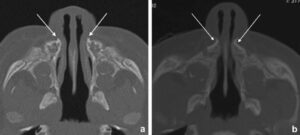

بعد ذلك، يتم تأكيد التشخيص بواسطة الأشعة. الأشعة البانورامية (OPG) تُظهر عرض الفك، وCBCT تُنتج نموذجًا ثلاثي الأبعاد دقيقًا للعظام.